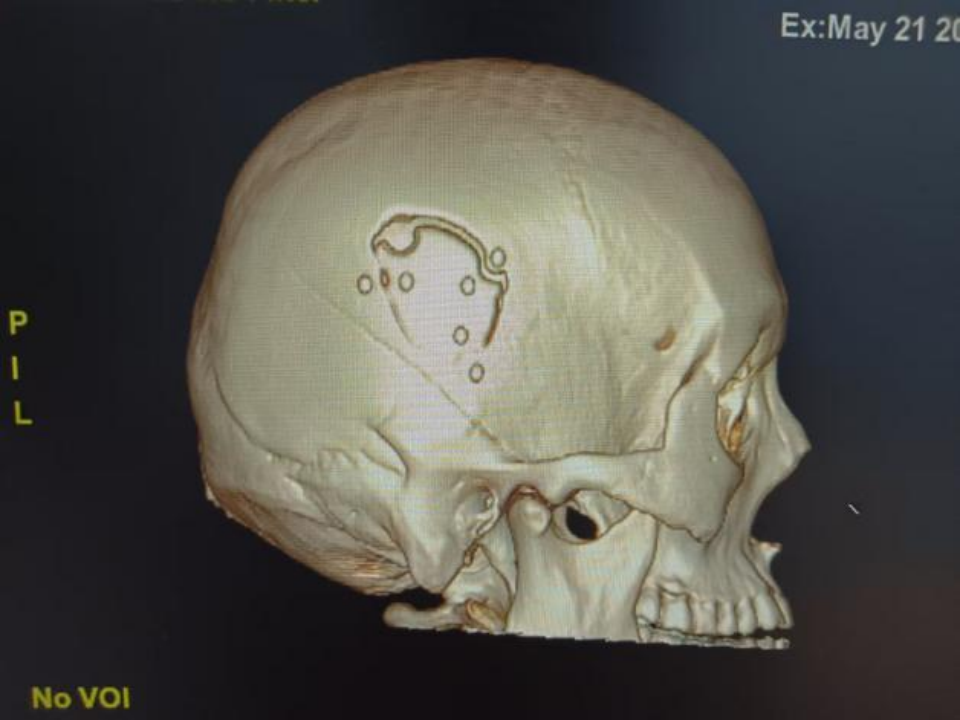

△术后颅脑CT三维重建

传统的手术方法是“问号形”或“马蹄形”切口切开头皮,根据血肿范围切除相当的骨瓣清除血肿,创伤大,切口一般在20cm左右,出血多,恢复慢。北京大学人民医院青岛医院采取神经内镜下清除硬脑外血肿,小切口,小骨窗,术中出血少,病人恢复快。

神经内镜下血肿清除术是一项先进的微创技术,就像让医生拥有了“透视眼”和“延长手”,能够在狭小的空间内完成更加精细的操作。北大人民青岛医院神经外科团队拥有丰富的颅脑创伤诊疗经验和精湛的微创手术技巧,配备高清神经内镜设备,对于颅脑创伤急症,建立了从急诊、医学影像到麻醉手术中心的绿色通道,为患者赢得宝贵的黄金时间。